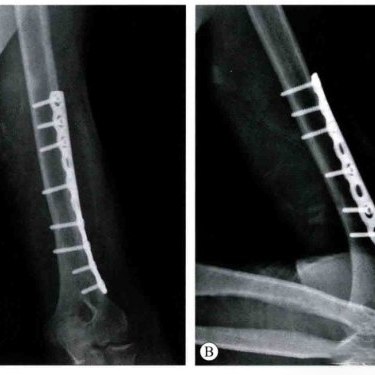

Пластины и винты часто используются для фиксации сломанных костей. Пластины представляют собой тонкие металлические полоски. Врачи прикрепляют их к кости с помощью винтов. Эти имплантаты удерживают кость вместе, поэтому она срастается ровно. Запирающие пластины обеспечивают дополнительную поддержку при сильных переломах или слабых костях. Patella Claw и специальные пластины для лодыжки и пятки помогают при тяжелых травмах.

Фиксирующие пластины помогают костям лучше заживать и обеспечивают надежную поддержку. Они останавливают кость от движения и помогают быстрее заживить.

Фиксирующие пластины хороши при переломах со смещением и сложных переломах.